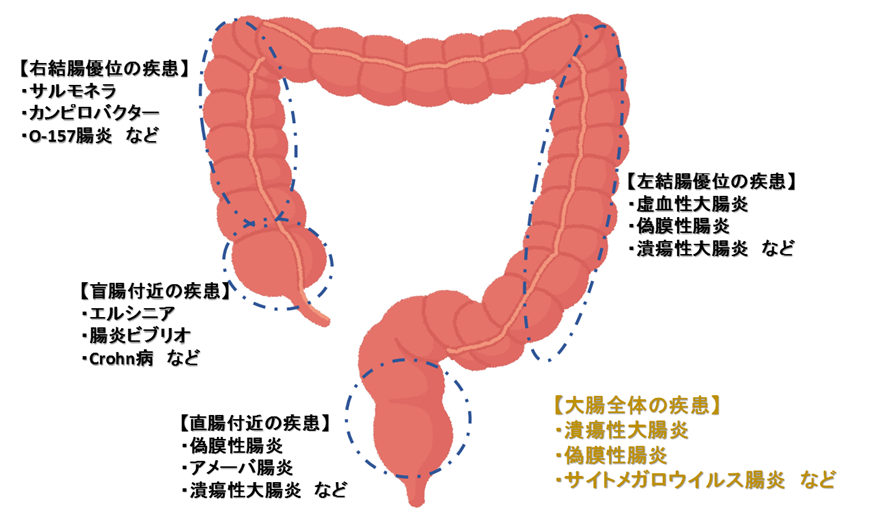

感染性大腸炎とは、感染によって生じる結腸または腸の炎症を指します。

- 細菌感染症:サルモネラ菌、大腸菌(E. coli) 、クロストリディオイデス・ディフィシル(C. diff)

- ウイルス感染症:ロタウイルス、アデノウイルス、ノロウイルス、サイトメガロウイルス

- 寄生虫感染症: Entamoeba histolytica

- 性感染症(STI): HIV 、クラミジア・トラコマチス、単純ヘルペス1型および2型、淋菌